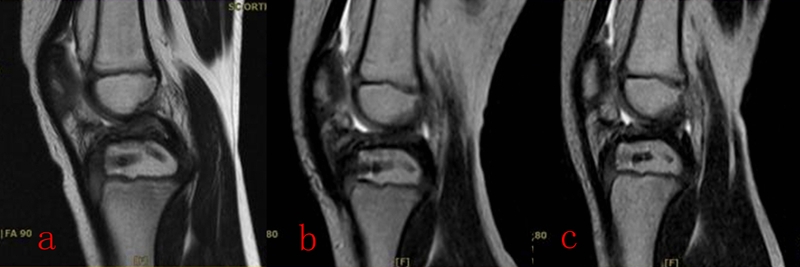

4岁男孩,游戏中跑步跌倒,扭伤左膝,迅速肿胀、疼痛。急诊DR和MRI显示前交叉韧带胫骨止点撕脱骨折,Meyers and Mckeever之III型。经镜下缝合桥技术,骨折解剖复位,固定可靠。术前MRI和术中透视,以及术后MRI如图20所示。术后3天,床旁悬吊屈膝可达90°,在伸膝支具保护下,护双拐下地平地行走,如图21所示。出院后接受运动康复及基础动作模式体能训练,并配合术后MRI复查及门诊随访。术前、术后及术后2月MRI如图22所示。

图22 a:术前MRI;b:术后MRI;c:术后2月MRI